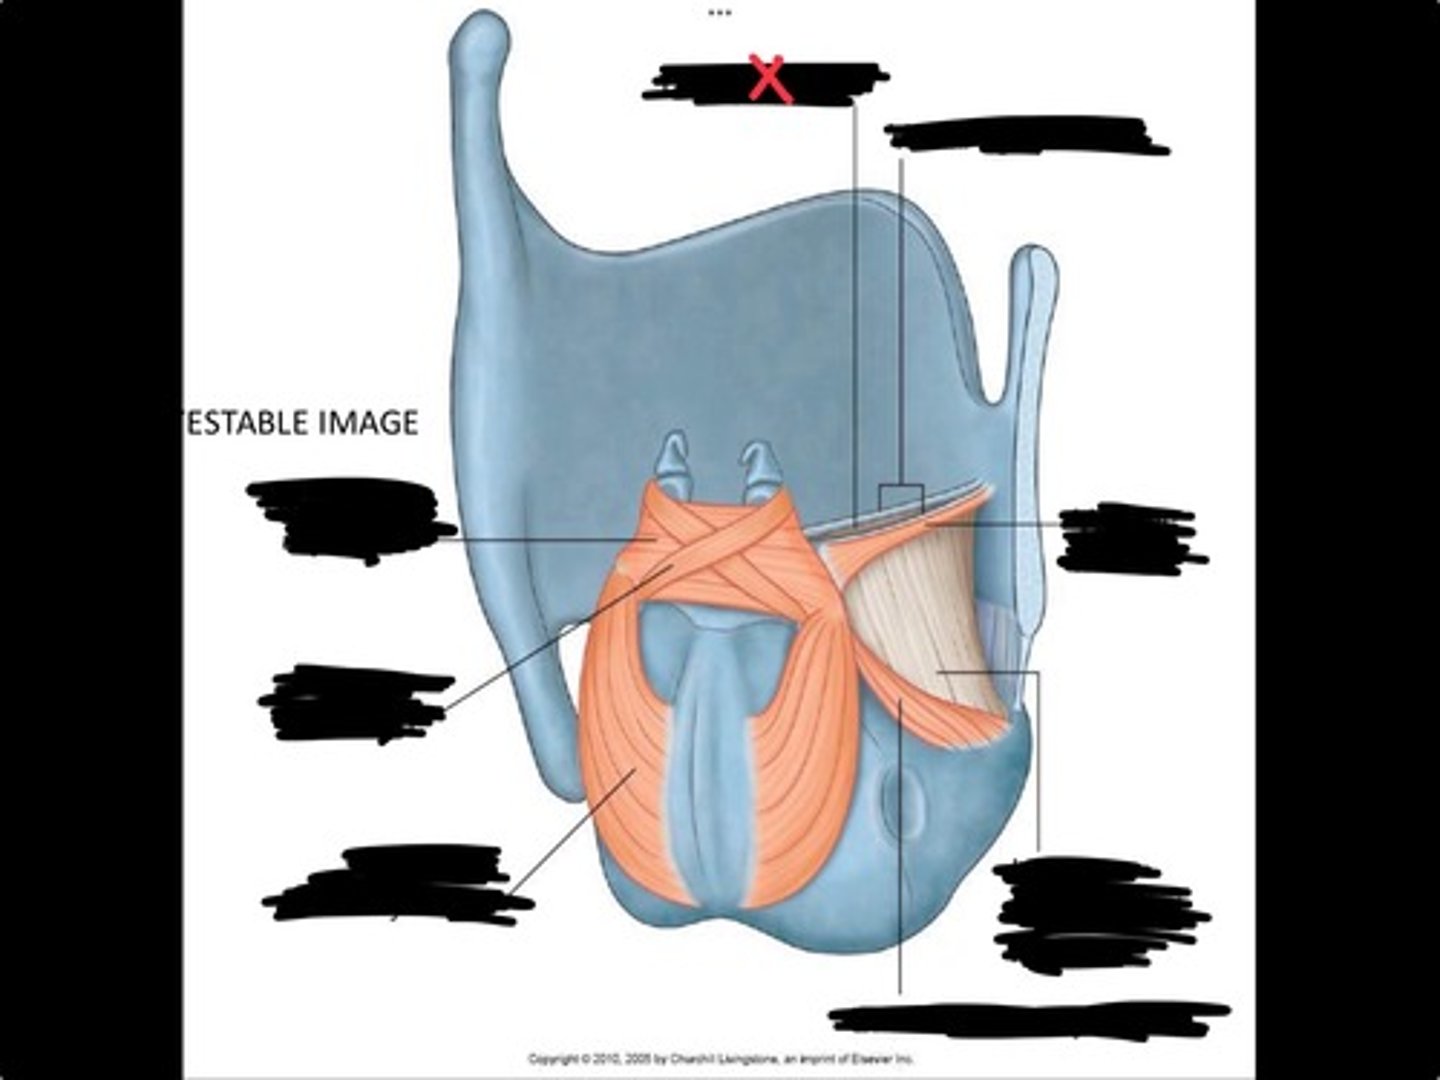

Vocal process of arytenoid

Conus elasticus

Vestibular ligament

Quadrangular membrane

Epiglottis

vocal ligament

Aryepiglottic ligament

Muscular process of arytenoid

Corniculate cartilage

Posterior crico arytenoid

oblique arytenoid

transverse artyenoid

Rima glottidis

Vocal ligament

Vocalis muscle

Lateral cricothyroid ligament

Lateral cricoartenoid